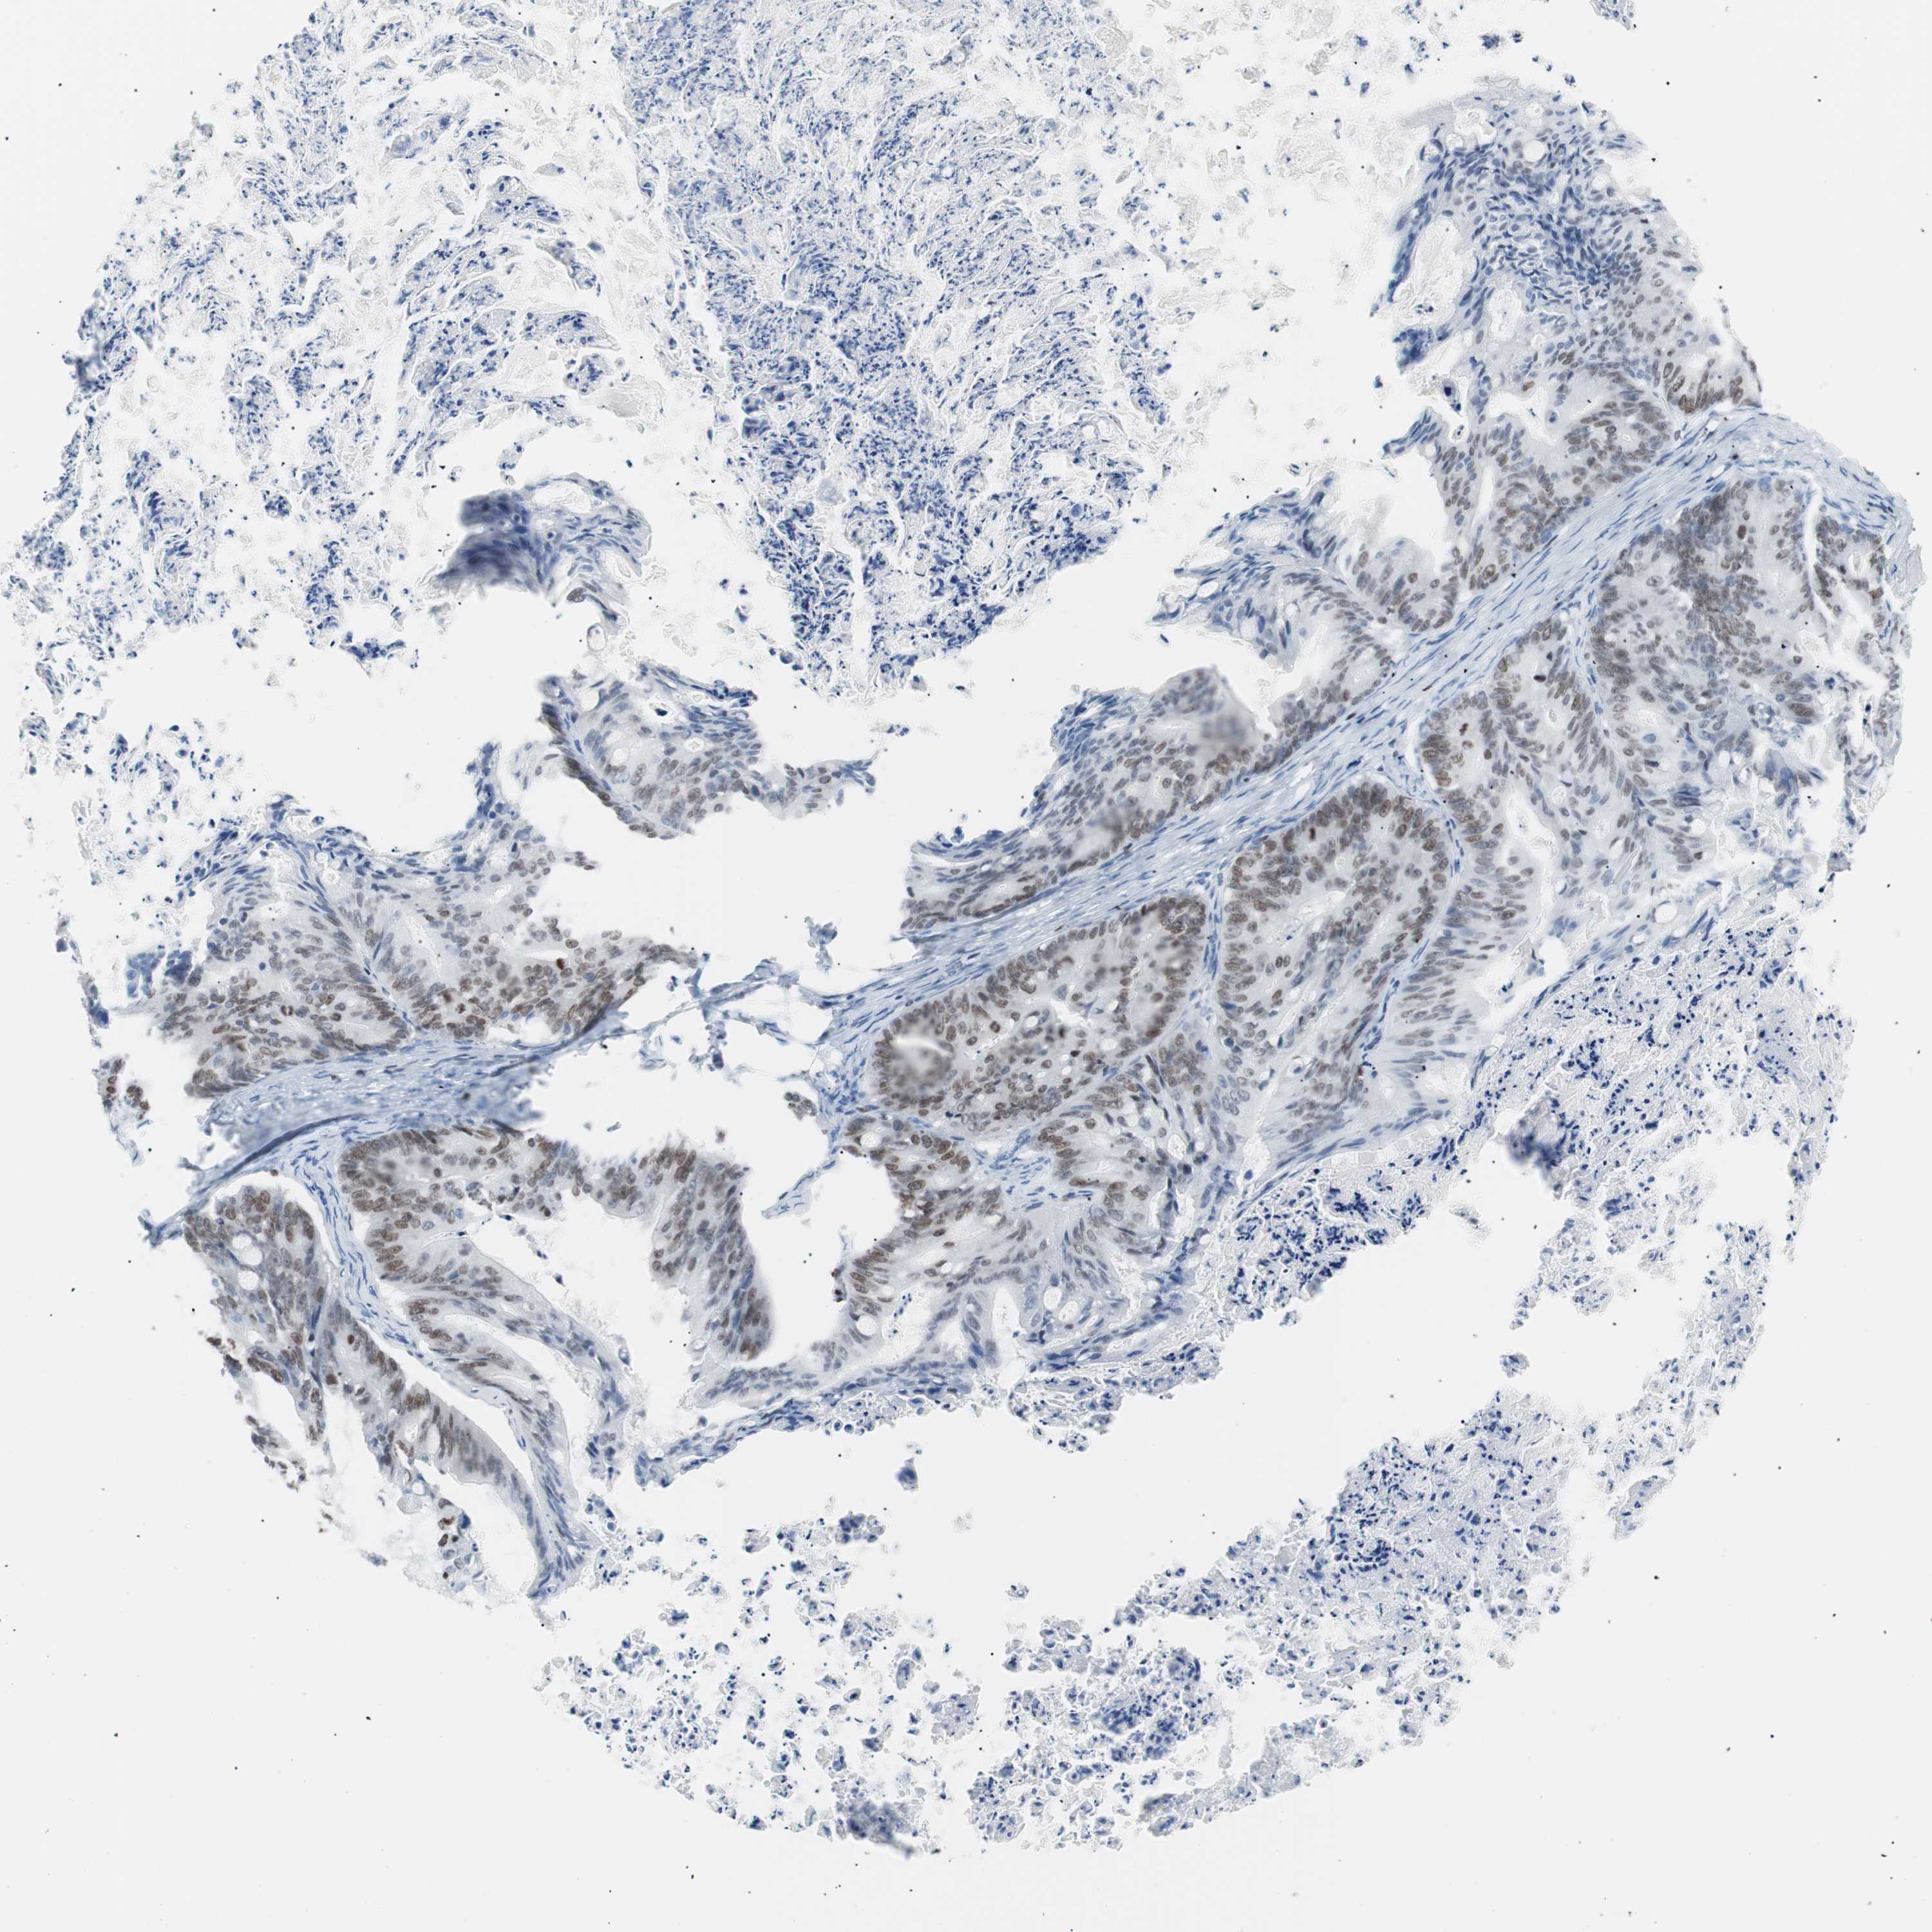

OVARIAN CANCER - Protein expressioni

A mouse-over function shows sample information and annotation data. Click on an image to view it in a full screen mode. Samples can be filtered based on level of antibody staining by selecting one or several of the following categories: high, medium, low and not detected. The assay and annotation is described here.

Note that samples used for immunohistochemistry by the Human Protein Atlas do not correspond to samples in the TCGA dataset.

Antibody stainingi

Antibody staining in the annotated cell types in the current human tissue is reported as not detected, low, medium, or high, based on conventional immunohistochemistry profiling in selected tissues. This score is based on the combination of the staining intensity and fraction of stained cells.

Each image is clickable and will lead to virtual microscopy that enables deeper exploration of all samples and also displays staining intensity scores, fraction scores and subcellular localization as well as patient and tissue information for each sample.

Antibody CAB004213

Staining

High

Medium

Low

Not detected

Intensity

Strong

Moderate

Weak

Negative

Quantity

>75%

75%-25%

<25%

None

Location

Nuclear

Cytoplasmic/membranous

Cytoplasmic/membranous,nuclear

Cystadenocarcinoma, serous, NOS

Carcinoma, endometroid

Carcinoma, NOS

Cystadenocarcinoma, mucinous, NOS